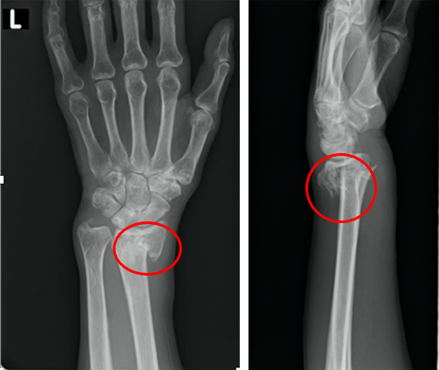

橈骨遠位端骨折は転倒した際に手をついて受傷しやすい骨折で骨折しやすい4大骨折の一つです。

骨粗しょう症の方など骨密度が低い方は軽く手をついた場合にも起こる事もあります。

主な治療方法として骨折部位に転位(ずれ)が生じていなければギプスによる固定を行い、転位が生じているようであれば手術により転位を元の位置に戻して金属プレートによる固定を行います。

近年は固定材料が改良されてきており、術後早期のリハビリテーションが可能となってきております。